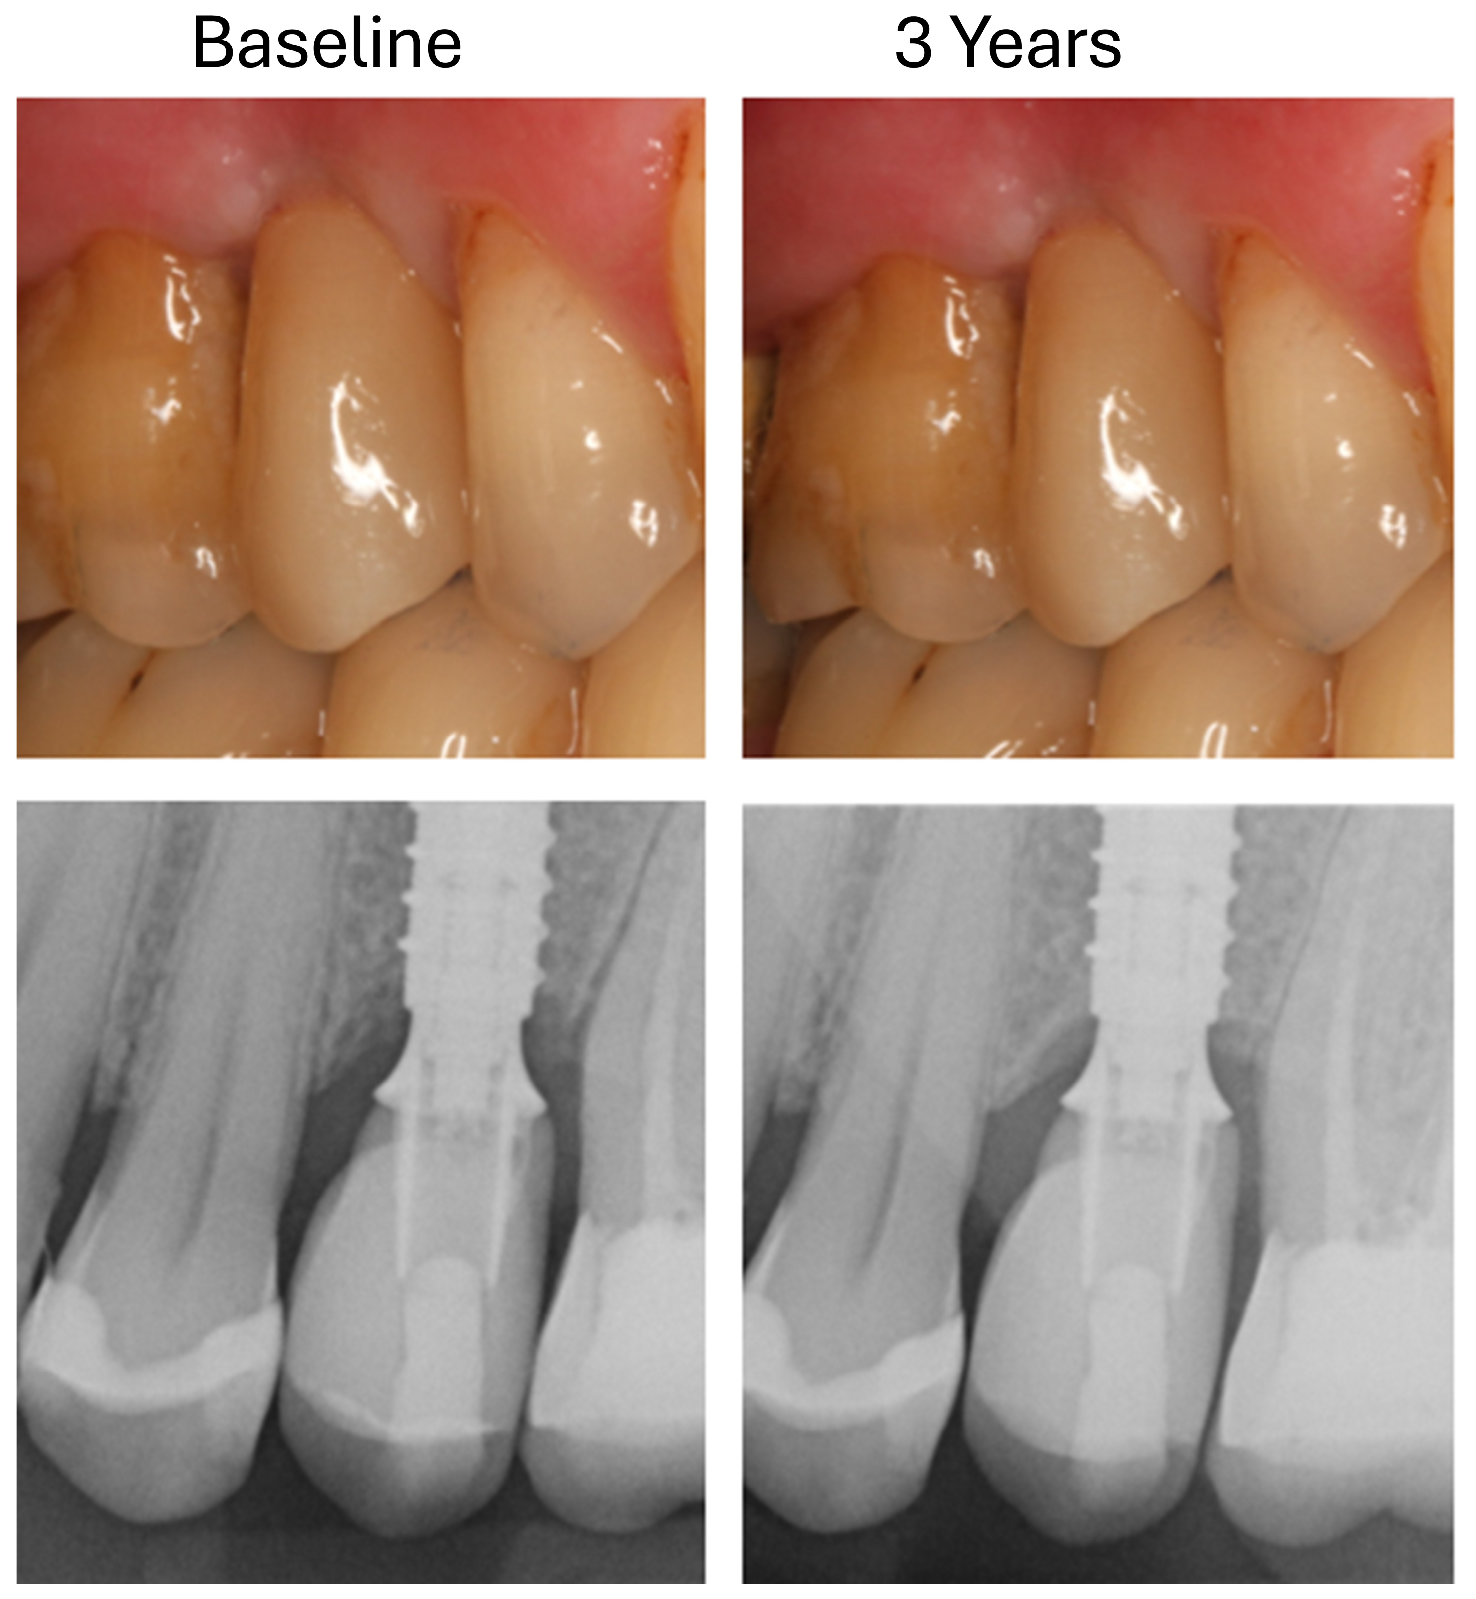

- T0: 1 week after insertion of the superstructure (baseline);

- T1: 3 years after implantation.

3.3. Changes in Marginal Bone Profile